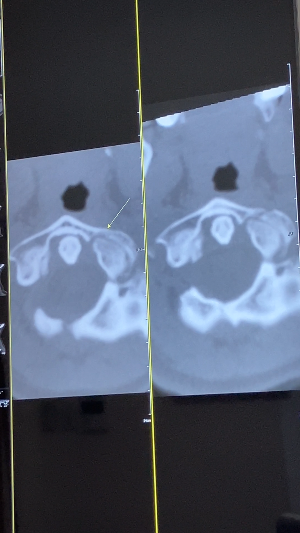

그럼 사진 한 번 볼까요?

이게 저번에 찍은 사진이고....

이게 3개월 뒤 오늘 찍은 사진인데...

IMG_2743.png

화면에 CT 사진이 뜨자마자

나와 남편, 그리고 선생님 모두

동시에 약속이라도 한 듯이

탄식을 내뱉었다.

일반인 눈으로도 보이시죠?

뼈가 이만큼 붙었어요.

외벽이 단단히 붙었어

네!!!보여요. 제 눈으로도

다리가 이어진게 보여요 선생님!!!

맞아요. 경추 1번이 골절이 심각했고

뼈 사이에 간극이 커서 걱정했는데

잘 붙어줬어요. 다행이에요.

생각보다 성과가 좋아 나도 기분이 좋네요

상태 양호해요.

선생님 근데 아래쪽은 아직 갭이 보여요

맞아요. 바깥쪽 뼈는 잘 붙어줬는데

아래쪽 뼈는 아직 덜 붙었어요.

이건 붙고 있어 시간이 좀 더 필요해요